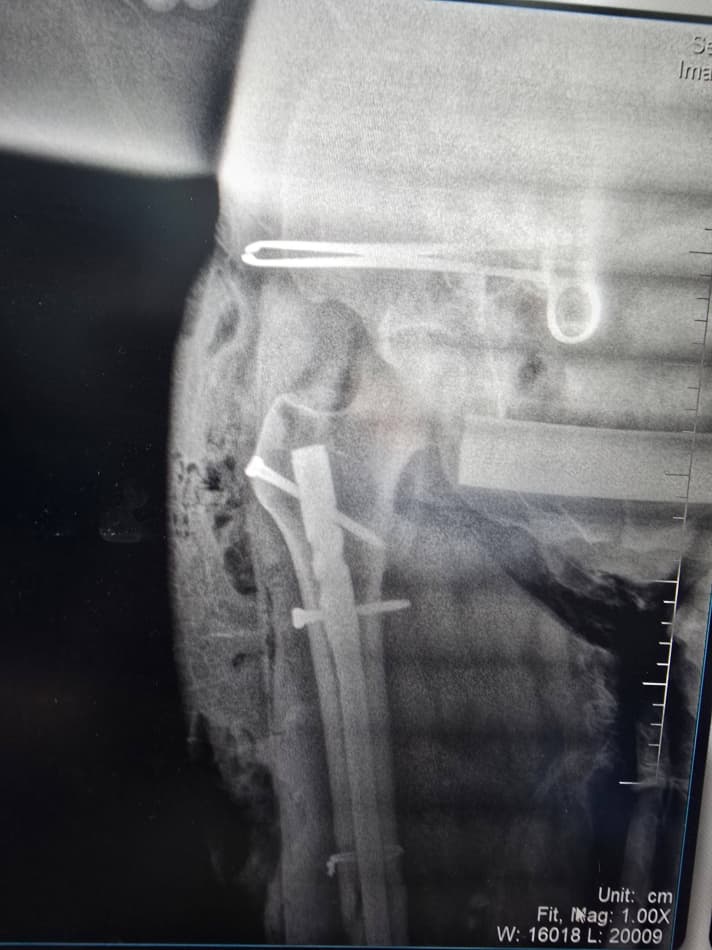

Маълум бўлишича, 1980 йилда туғилган бемор жорий йил 8 апрель куни уч ғилдиракли юк мотоциклида йўл-транспорт ҳодисасига учраб, турли даражадаги тан жароҳатларини олган. Тиббий кўрик натижасида беморга бош мия чайқалиши билан бирга чап оёғи сон суягининг ўрта учлигида очиқ синиш ташхиси қўйилди. Бундай ҳолатларда тезкор ва юқори малакали тиббий ёрдам ҳаётий аҳамият касб этади.

Шифокорлар томонидан беморнинг ҳолати чуқур ўрганилиб, замонавий усулда жарроҳлик амалиёти ўтказишга қарор қилинди. Хусусан, чап сон суягини тиклаш мақсадида каминвазив усулда блокланган интрамедулляр остеосинтез (БІОС) амалиёти бажарилди. Бу усул суяк ичига махсус металл имплант ўрнатиш орқали синишни ичкаридан мустаҳкамлашга хизмат қилади. Натижада операция кам жароҳат билан ўтади, қон йўқотиш камаяди ва беморнинг соғайиб, оёққа туриш жараёни тезлашади.